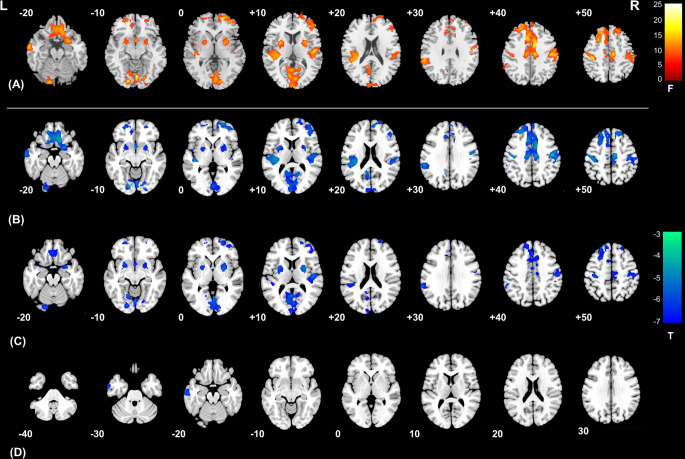

To investigate the grey matter volume (GMV) changes and uremic metabolites in end-stage kidney disease (ESKD) patients with mild cognitive impairment (MCI) (ESKD-MCI) and further examine the classification and diagnostic efficacy of these features for ESKD-MCI patients. A total of 65 patients with ESKD, including 34 ESKD-MCI and 31 with non-cognitive impairment (ESKD-NCI), and 55 health controls (HCs) were enrolled. All participants underwent brain structural magnetic resonance imaging (MRI) scanning and Montreal cognitive assessment test. Clinical characteristics and GMV differences among these three groups were analyzed. In addition, mediation analysis was performed to determine the mediating effect of GMV changes on the association between clinical risk factors and MCI. Finally, support vector machine were employed to examine the classification and diagnostic efficacy of GMV changes and clinical features for MCI. Both patient groups exhibited widespread structural brain injury compared with the HCs. Moreover, compared with ESKD-NCI, ESKD-MCI patients demonstrated reduced GMV specifically in the left middle temporal gyrus and inferior temporal gyrus. Notably, these GMV changes completely mediates the effect of serum phosphorus levels on MCI. Furthermore, imaging features rather than serum phosphorus levels had good classification and diagnostic efficacy for ESKD-MCI. Our findings underscore the significance of the left temporal gyrus as a pivotal brain region in ESKD-MCI patients, fully mediating the link between uremic metabolite and MCI. GMV alterations presents a promising avenue for effectively detecting MCI in individuals with ESKD.